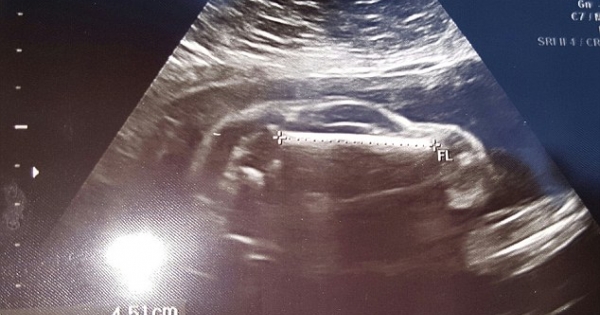

▼這張超聲波照片看起來很像跑車,就連車窗、車輪都看得很清楚。

▼網友們紛紛表示,「這絕對會引發中年危機」。